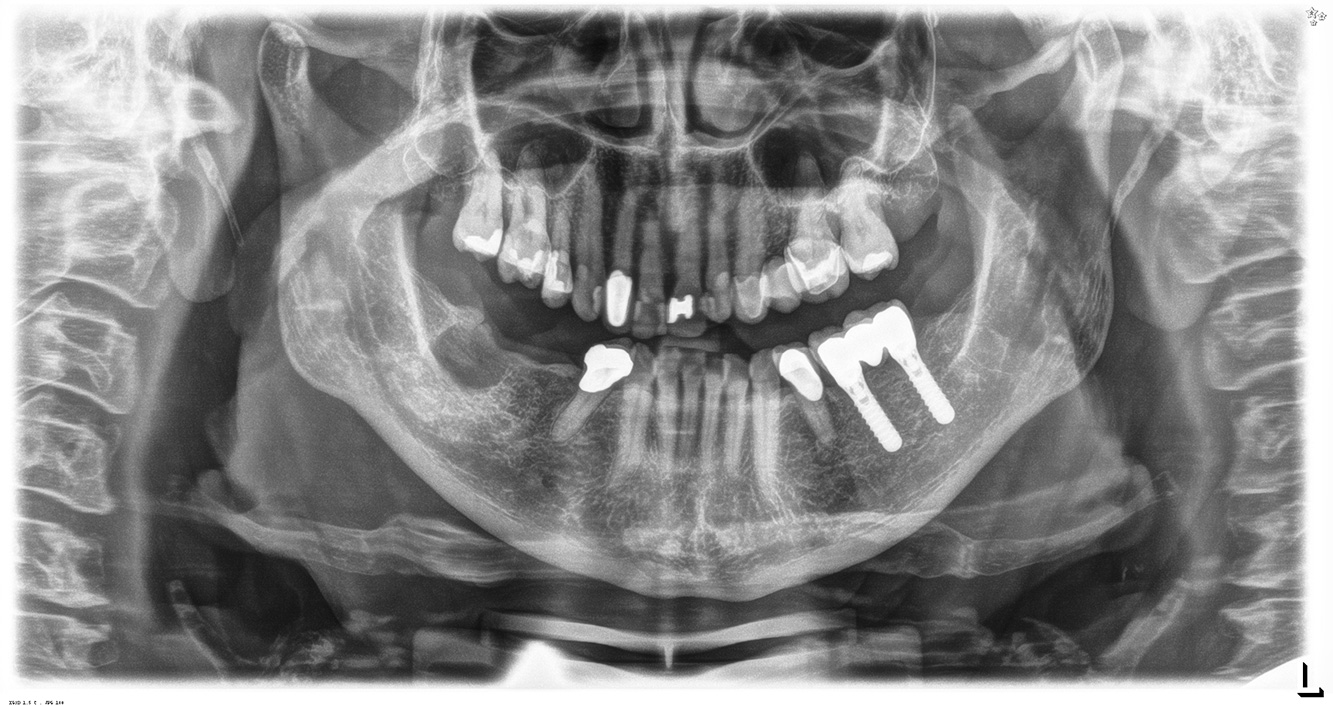

The 68-year-old patient has no general health conditions and is not taking any medication that may be relevant to her oral health, and her lifestyle does not pose any particular risk. The patient has two dental implants (3rd quadrant, for five years) and a previous case of periodontal disease (stage IV, grade B periodontitis) with tooth loss. Currently the periodontal conditions are stable. However, periodontitis significantly increases the biological complications of implantations and there is a risk of implant loss (21). Four recommendations can be determined for the prophylaxis session.

As the patient does not have any particular risk factors with specific dental implications, the requirements determined from her current state of oral health are crucial. Here, it is recommended that a thorough assessment of periodontal condition be carried out once a year. This will ensure that any potential progression of the previous periodontal disease or development of peri-implantitis can be responded to in good time.

In terms of instruments, specific procedures are required for use with implants. In order to preserve the surface of the implant while cleaning it effectively, it is essential to choose suitable powders and instruments such as the targeted use of air polishing devices with special periodontal tips. Which powder is most suitable can be determined according to the needs and risk. For example, in addition to the appropriate degree of abrasion, dietary requirements (including sugar-free, low-salt) may also be taken into account.

Because the patient has implants and a history of periodontal disease, she is at risk of developing peri-implantitis. It is therefore recommended that she attend a recall session every three to four months.